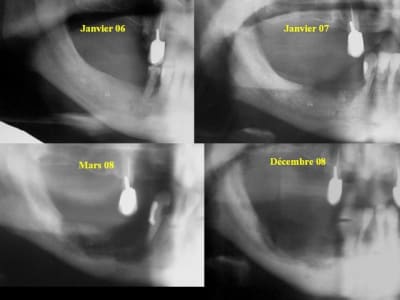

Les patients perdent leur mandibule à petit feu si ils ne meurent pas avant avec de fréquents épisodes infectieux ....

Ils est très difficile de les appareiller.